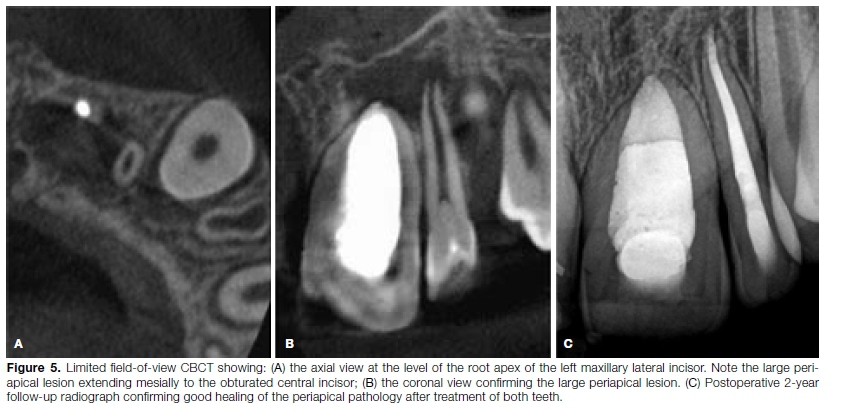

Ten months later, the patient presented for a follow-up visit. Vitality testing was performed again on the adjacent teeth, and the maxillary left lateral incisor was found to be nonvital. The follow-up, low-resolution CBCT revealed a large periapical area around the root tip of the left lateral incisor (Figures 5A-B) that presented with Type II dens invaginatus. The tooth was treated similarly to the central incisor by removing the necrotic pulp tissue and packing MTA close to the open apex of the root canal (using the same technique as described above), followed by obturation with heated gutta-percha.

A two-year, postoperative, periapical follow-up radiograph revealed complete resolution of the periapical pathology (Figure 5C).